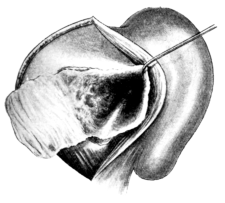

| 317. | Lateral Rhinotomy | 620 |

| 318. | Rouge’s Operation. First stage | 622 |

| 319. | Rouge’s Operation. Second stage | 623 |